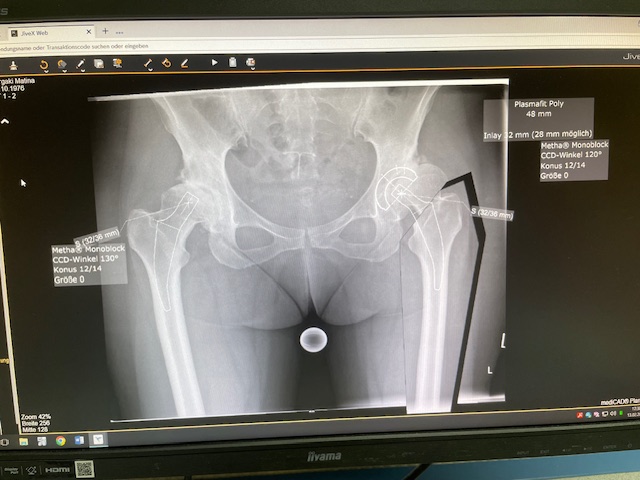

Ο προεγχειρητικός ψηφιακός σχεδιασμός

Ο προεγχειρητικός ψηφιακός σχεδιασμός ήταν ιδιαίτερα μεθοδικός και συγκεκριμένος. Η ακτινογραφία λεκάνης της ασθενούς εισήχθη σε ειδικό λογισμικό στον υπολογιστή, το οποίο επέτρεψε τον ακριβή προγραμματισμό της καινούριας θέσης της άρθρωσης.

Μέσω του ψηφιακού αυτού σχεδιασμού, υπολογίστηκε με ακρίβεια το μέγεθος και ο τύπος των προθέσεων, η γωνία του κώνου, καθώς και η σωστή ανατομική τοποθέτηση των μοσχευμάτων. ώστε να επιτευχθεί τέλειος ισοσκελισμός των κάτω άκρων και να αποφευχθεί οποιαδήποτε διαφορά μήκους μετεγχειρητικά!!!

Πρόκειται για ένα εξαιρετικά σημαντικό στάδιο, καθώς εξασφαλίζει τη μέγιστη δυνατή ακρίβεια, ταχύτητα και αποτελεσματικότητα κατά τη διάρκεια της επέμβασης. Επιπλέον, συμβάλλει στην άριστη λειτουργικότητα του ισχίου καθώς και να επιτευχθεί τέλειος ισοσκελισμός των κάτω άκρων και να αποφευχθεί οποιαδήποτε διαφορά μήκους μετεγχειρητικά!!!

Ο προεγχειρητικός ψηφιακός σχεδιασμός αποτελεί πάντα πλήρως εξατομικευμένο πλάνο, προσαρμοσμένο στα ανατομικά χαρακτηριστικά και τις ανάγκες του κάθε ασθενούς, και είναι καθοριστικός για την επιτυχία της επέμβασης !!!